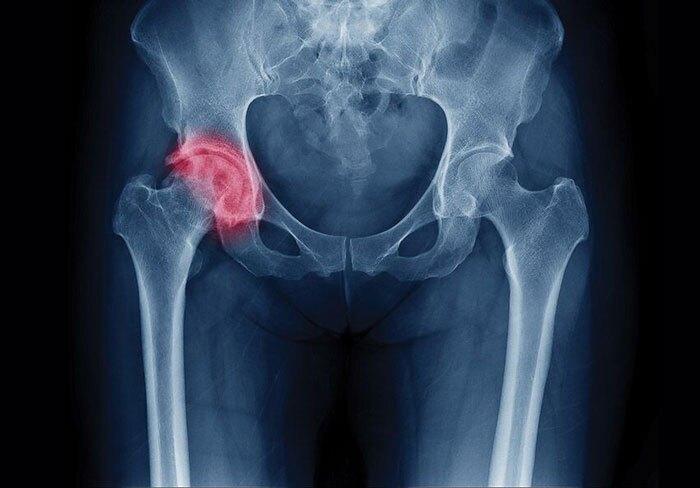

منشا دردهای لگنی و نحوه درمان آنها

به گزارش خبرنگار حوزه کلینیک گروه علمی پزشکی باشگاه خبرنگاران جوان، افشین طاهری اعظم، متخصص ارتوپد و فلوشیپ جراحی لگن در خصوص دوران نقاهت بعد از جراحی لگن اظهار کرد: درمان های جراحی مشکلات لگن شامل درمان های تعویض مفصلی و غیر تعویض مفصلی است. بعضی از مشکلات لگن مثل شکستگی ها امکان دارد نیاز به ثابت کردن شکستگی های ایجاد شده در لگن داشته باشد.

او افزود: باید به این نکته توجه داشت، بعضی از شکستگیها بسیار مهم هستند بنابراین اگر یکی از افراد خانواده دچار شکستگی مفصل ران شد به ویژه افراد مسن، بهتر است که در همان ۲۴ ساعت اول از آغاز اتفاق، جراحی ثابت کردن لگن انجام شود.

طاهری اعظم تصریح کرد: بیمارانی که دچار تخریب بسیار شدید در مفصل ران، آرتروز بسیار شدید و در رفتگیهای مادر زادی میشوند، مشکلات و درد زیادی را تحمل میکنند.

این متخصص ارتوپد در خصوص اینکه آیا هر درد لگنی نیاز به جراحی دارد، یا با دارو درمان میشود، گفت: درصد بسیار کمی از افرادی که درد لگن دارند، حتما نیاز به جراحی پیدا خواهند کرد.

او ادامه داد: منشا دردهای به وجود آمده در لگن، یا از خود لگن است یا دردهایی در قسمتهایی مانند ستون فقرات و دیسکهای بیرون زده، باعث ایجاد عارضه در ناحیه کشاله ران و لگن میشود.

طاهری اعظم گفت: دردی که مختص خود مفصل ران است معمولا در مراحل اولیه اگر تشخیص و درمان شوند، بدون نیاز به عملهای جراحی میتوان این دردها را کاهش داد، اما تاریخچه طبیعی بعضی از دردهای لگن این الزام را ایجاد میکند که در نهایت برای رهایی از دردها نیاز به جراحی پیش بیاید.

او افزود: اگر بعد از درمانی که برای بیمار در نظر گرفته میشود، علامتهای مرتبط با مشکلات لگنی او از بین نرفت و بیماری علی رغم درمان پیشرفت کرد، برای این افراد حتما عملهای جراحی لگن توصیه میشود.